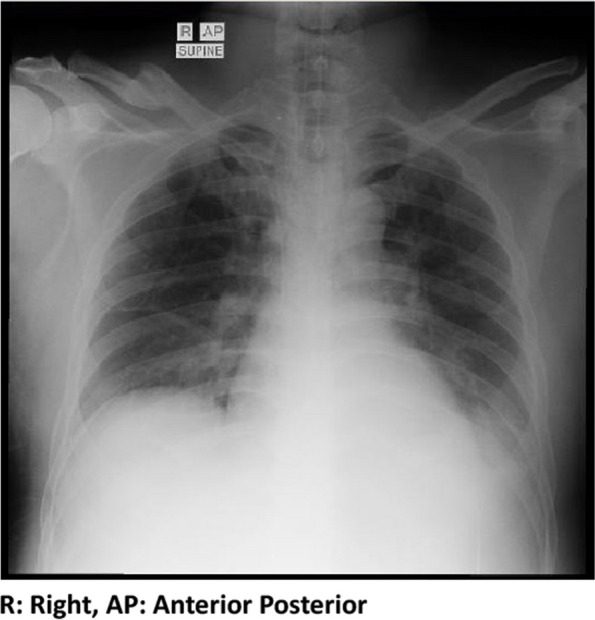

Case presentation: A 46-year-old man was brought to the Emergency Room (ER) because of fever and chills for 6 days. Complaints were accompanied by nausea and vomiting three times a day. The patient also experienced headaches, weakness, coughing, and a runny nose after two days of admission. The patient had no history of traveling from a malaria-endemic area. The patient was transferred from the Emergency Department (ED) to the High Care Unit (HCU), and during 1 day of intensive care at the HCU, there was a clinical deterioration characterized by dyspnea, icteric sclerae, acral edema, tenderness in both calves, and rash in the abdominal area. Due to worsening respiratory function, the patient was placed on a ventilator. During intensive treatment, the patient continued to show deterioration. The clinical findings suggested a possible feature of Weil's disease or fulminant hepatitis, and although the patient was in intensive care, there was no clinically significant improvement. Furthermore, microscopic blood smear examination and rapid diagnostic tests (RDTs) for malaria were carried out on the 4th day of treatment with negative results. As there was no clinically significant improvement, it was decided to take a blood smear and repeat RDT on the twelfth day, which showed a positive result for falciparum malaria. Subsequently, artesunate was administered intravenously, and the patient's condition began to improve with a negative parasite count the following day. The patient was discharged in good clinical condition on day 25 of treatment.